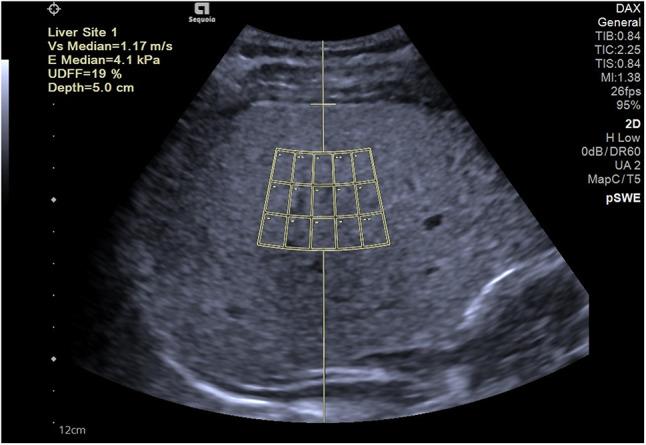

This retrospective study involved 89 patients diagnosed with WD. The demographic characteristics, body mass index (BMI), conventional ultrasound examination, liver shear wave elastography, and ultrasound-derived fat fraction (UDFF) detection data were collected and statistically analyzed. The degree of hepatic steatosis was evaluated using the visual scoring method known as the Hamaguchi score. The Bland-Altman plot was used to analyze the intra-observer and inter-observer consistency of UDFF measurements. The Spearman correlation analysis was conducted to explore the correlations among BMI, UDFF, and the Hamaguchi score. Additionally, confounding factors were included to analyze whether UDFF was an independent influencing factor for WD hepatic steatosis. The receiver operating characteristic (ROC) curve was utilized to determine the cutoff value of UDFF for diagnosing WD hepatic steatosis and its diagnostic efficacy.

The Bland-Altman analysis showed bias values of 5.7% and 1.1% for intra-observer variability of a junior and a senior sonologist, respectively, and 14.9% for inter-observer variability. Univariate analysis showed no significant correlation between BMI and the Hamaguchi score ( = 0.08,  = 0.478). However, there was a positive correlation between UDFF and the Hamaguchi score ( = 0.71,  < 0.001). Multivariate analysis indicated a significant correlation between UDFF and WD hepatic steatosis, with a regression coefficient of 1.243, OR of 3.465, and 95% CI of 1.617–10.51 ( = 0.008). ROC curve analysis demonstrated that the optimal cutoff value of UDFF for diagnosing WD hepatic steatosis was 4.5%, with an AUROC of 0.80 (95% CI: 71 − 90%), sensitivity of 90%, and specificity of 80%.